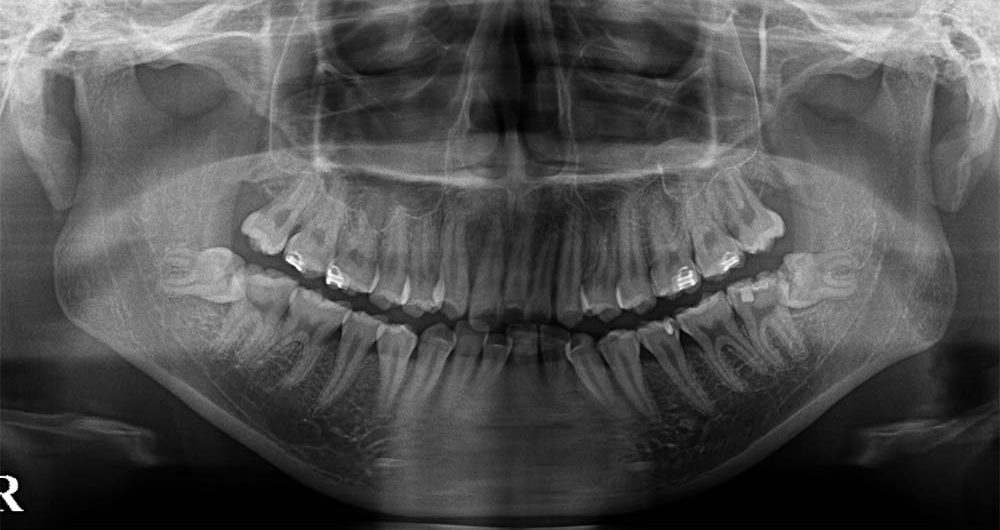

70代男性

ケース4:右下の奥歯が痛む

県内の歯科医院より紹介頂き受診されました。初診の当日に処置を行っています。

横になった歯の下に神経が走っていたためCTにて位置関係を3次元的に確認したうえで、5mm程度の切開を行い歯の頭の部分を削って抜きました。2糸縫って終わっています。

なお、高血圧で治療をされていたため生体モニター(心電図、血圧計、酸素飽和度等)の監視下に処置を行っています。

術後は紹介先で経過を診て頂いていますが、少しの腫れはあったようですが痺れ等はなかったようです。

- 所要時間

- 20分程度

- 費用

- ¥9,000(健康保険内)